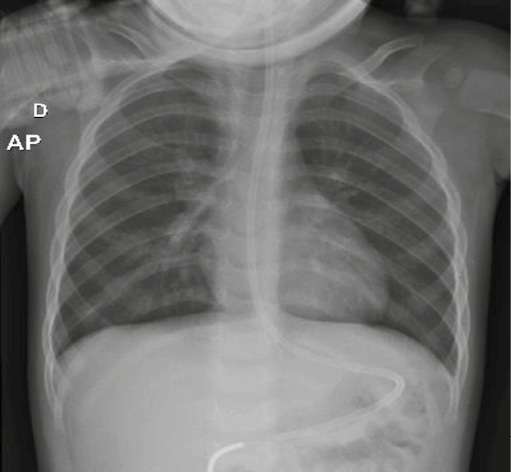

A radiografia de tórax inicial revelou padrão de hipersinsuflação pulmonar, sem consolidações ou opacidades sugestivas de pneumonia (Figura 1). Exames laboratoriais sem compatibilidade com infecção bacteriana, com painel viral rápido negativo. Apesar da terapêutica empregada, manteve quadro de taquipneia e taquicardia com desconforto respiratório moderado/grave (tiragem subcostal, intercostal e de fúrcula esternal, expiração ativa), AP rude com sibilância difusa, Glasgow 14, sem alterações hemodinâmicas.

Figura 1 - Radiografia de tórax na admissão evidenciando padrão típico de hiperinsuflação.

Fonte: arquivo dos autores